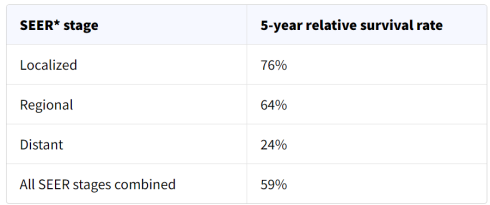

میزان بقا برای استئوسارکوم

میزان بقا میتواند به شما ایده دهد که چند درصد از افراد مبتلا به همان نوع و مرحله سرطان، مدت معینی (معمولاً 5 سال) پس از تشخیص هنوز زنده هستند. آنها نمیتوانند به شما بگویند که یک فرد چقدر زنده خواهد ماند اما ممکن است به شما کمک کند تا درک بهتری از احتمال موفقیت روند درمانی خود داشته باشید.

به خاطر داشته باشید که میزان بقا عددی تخمینی است و اغلب بر اساس نتایج قبلی تعداد زیادی از افرادی است که سرطان خاصی داشتند اما آنها نمیتوانند پیش بینی کنند که در مورد فرد خاصی چه اتفاقی خواهد افتاد. این آمار میتواند گیج کننده باشد و ممکن است شما را به پرسیدن سوالات بیشتری سوق دهد. از پزشک خود بپرسید که چگونه این اعداد ممکن است برای شما (یا فرزندتان) اعمال شود.

نرخ بقای نسبی 5 ساله چیست؟

نرخ بقای نسبی افراد مبتلا به همان نوع و مرحله سرطان را با افراد موجود در کل جمعیت مقایسه میکند. به عنوان مثال، اگر نرخ بقای نسبی 5 ساله برای مرحله خاصی از استئوسارکوم 70 درصد باشد، به این معنی است که احتمال زنده ماندن افرادی که به آن سرطان مبتلا هستند نسبت به افرادی که آن سرطان را ندارند برای ۵ سال پس از تشخیص ابتلا، به طور متوسط حدود 70 درصد است.

انجمن سرطان آمریکا برای ارائه آمار بقای انواع مختلف سرطان به اطلاعات پایگاه داده نظارت، اپیدمیولوژی و نتایج نهایی (Surveillance, Epidemiology, and End Results یا SEER) که توسط موسسه ملی سرطان (NCI یا National Cancer Institute) نگهداری میشود، متکی است.

پایگاه داده SEER نرخ بقای نسبی 5 ساله استئوسارکوم در ایالات متحده را بر اساس میزان گسترش سرطان دنبال میکند. با این حال، پایگاه داده SEER سرطانها را بر اساس مراحل MSTS یا TNM (مرحله 1، مرحله 2، مرحله 3 و غیره) گروه بندی نمیکند. در عوض، سرطانها را به مراحل موضعی، منطقه ای و دور دسته بندی میکند:

- موضعی (Localized): هیچ نشانه ای از گسترش سرطان به خارج از استخوان و جایی که شروع شده است، وجود ندارد.

- منطقه ای (Regional): سرطان در خارج از استخوان و به ساختارهای مجاور گسترش یافته یا به غدد لنفاوی مجاور رسیده است.

- دور (Distant): سرطان به قسمتهای دور بدن مانند ریهها یا استخوانهای سایر قسمتهای بدن گسترش یافته است.

نرخ بقای نسبی 5 ساله برای استئوسارکوم

این اعداد بر أساس اطلاعات افرادی است که بین سالهای 2012 تا 2018 مبتلا به استئوسارکوم تشخیص داده شده اند.

درک اعداد

- این اعداد فقط برای مرحله سرطان در هنگام اولین تشخیص صدق میکنند. اگر سرطان رشد کند، گسترش یابد یا پس از درمان عود کند، بعداً اعمال نمیشوند.

- این اعداد همه چیز را در نظر نمیگیرند. میزان بقا بر اساس میزان گسترش سرطان گروه بندی میشود اما عوامل دیگری مانند مواردی که در زیر ذکر شده است نیز میتوانند بر دیدگاه فرد تأثیر بگذارند.

- افرادی که اکنون مبتلا به استئوسارکوم تشخیص داده شده اند، ممکن است چشم انداز بهتری نسبت به این اعداد داشته باشند. درمانها با گذشت زمان بهبود مییابند و این اعداد بر اساس افرادی است که حداقل 5 سال زودتر تشخیص داده شده و درمان شده اند.